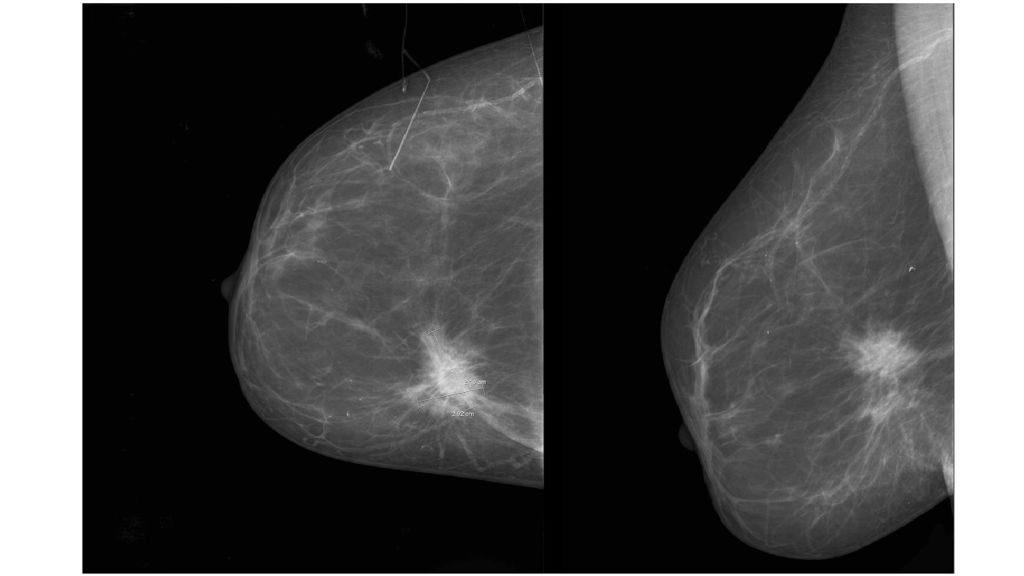

Диагностировать липому может врач хирург после визуального осмотра и пальпации места новообразования. По рекомендации врача может потребоваться УЗИ мягких тканей, маммография или биопсия с цитологическим или гистологическим исследованием.

По рекомендации врача может потребоваться УЗИ мягких тканей, маммография или биопсия с цитологическим или гистологическим исследованием.